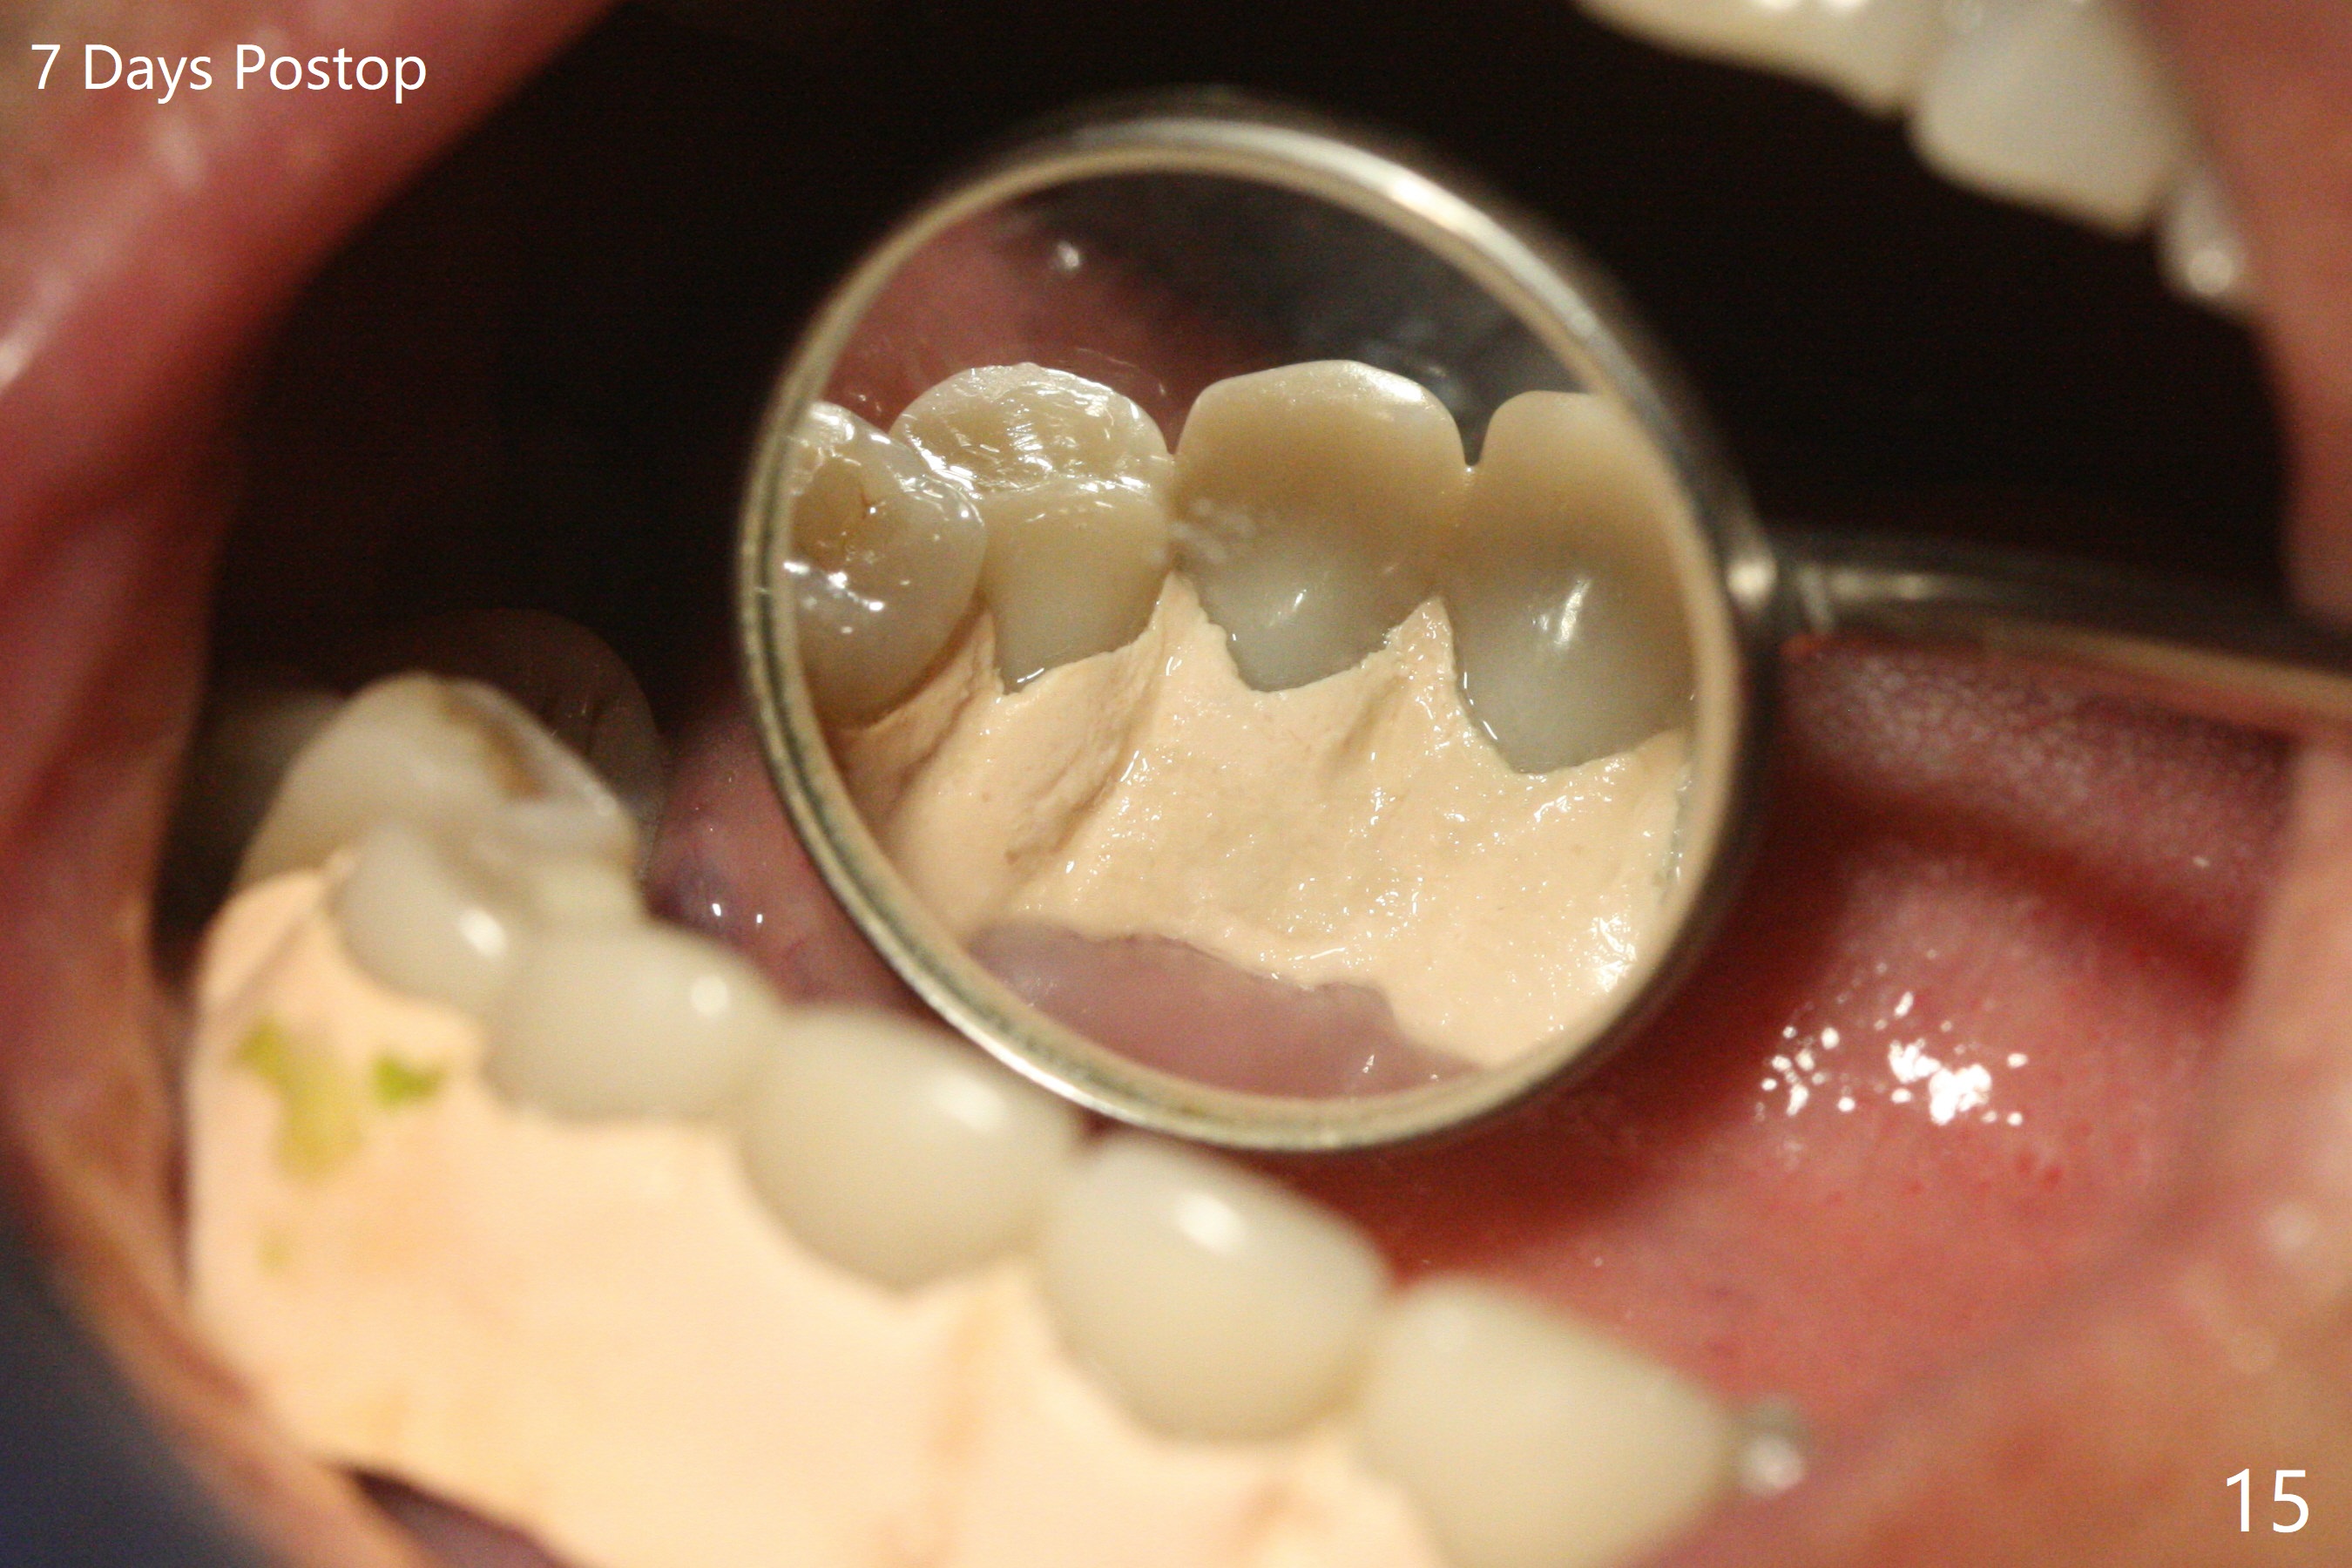

The implants remain asymptomatic years months post cementation (Fig.12), while the one at #27 is associated with buccal and lingual swelling and hemorrhage and bone loss (Fig.13).  There is bone loss distal to #27 without symptom 3 years 9 months post cementation (Fig.12).  Periimplantitis develops buccal and lingual 4 years 5 months post cementation (coronavirus, Fig.13).  Sticky bone and PRF are used after debridement.  There is no discomfort 7 days postop (Fig.14,15).